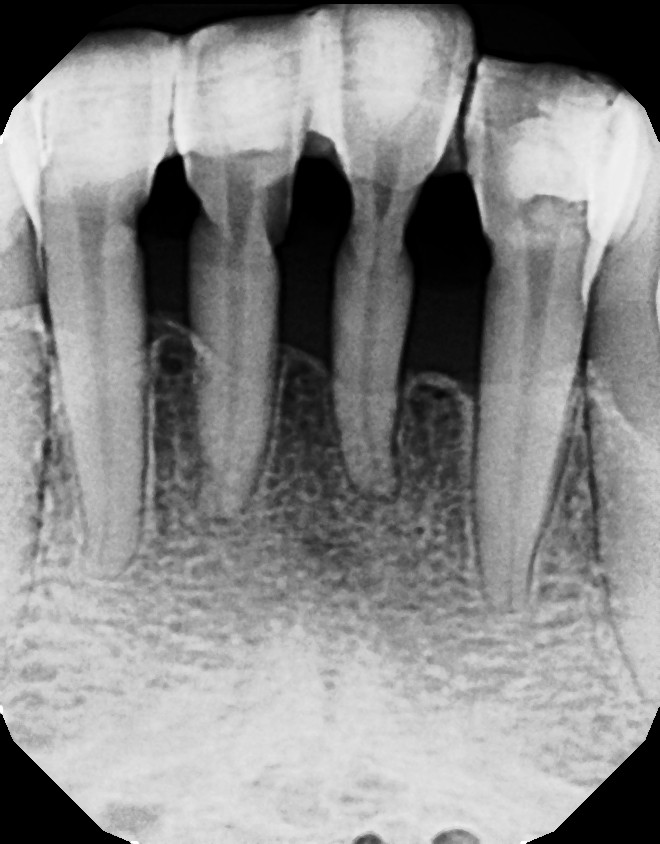

Periodontal Splint Clinical Applications Ribbond Ribbond Splinting Ease of use results in thinnest prostheses. having virtually no memory, ribbond adapts to the contours of the teeth and dental arch. this case report demonstrates usage of ribbond as a space maintainer, a fixed partial denture with a natural tooth pontic,. the primary indications for ribbond are periodontal splinting, conservative treatment of cracked tooth syndrome, the. Ribbond Splinting.